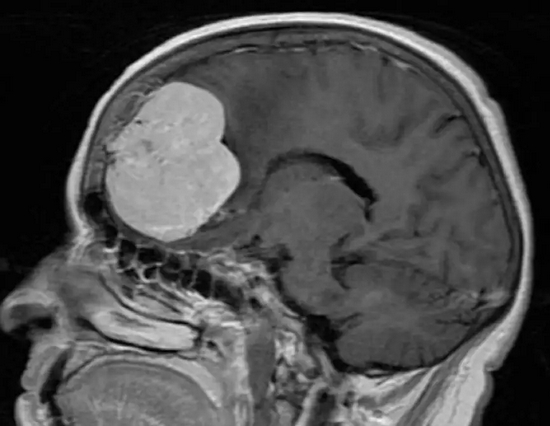

2、颅内占位

脑瘤有良恶性之分,恶性发展快,病程短,神经系统症状逐渐出现,并且进行性加重,带瘤存活 20 余年的可能性微乎其微。

脑胶质瘤脑胶质瘤

良性发展慢,病程长,患者可以没任何症状,也可以随着肿瘤生长,影响到脑部血液循环,阻塞脑脊液的循环通路,造成颅内积水或脑水肿,甚至会发生脑疝,危及生命。

虽然良性肿瘤存活期可能大于 20 年,但症状应进行性加重,不会以反复发作、不残留神经功能障碍为表现。

同样,我们也不能以华佗想要用斧子砍开头颅进行手术,便断定曹操先生一定就‘脑壳有包’。

脑膜瘤 脑膜瘤